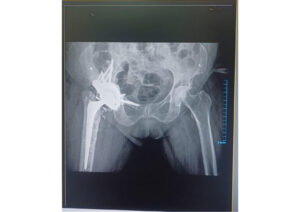

Post-op Outcome:

The revision hip replacement surgery was completed. The custom FTL cup fit seamlessly into the reconstructed acetabulum, with accurate screw fixation achieved using the provided drilling guides.

Early postoperative assessments demonstrated stable fixation, restored hip biomechanics, and improved functional outcomes.